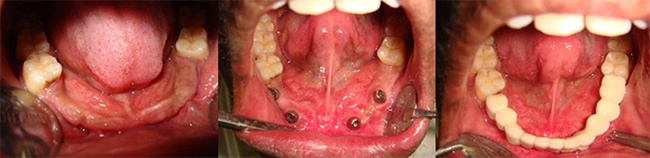

Full mouth Rehabilitation:

Dental Implant Prosthesis